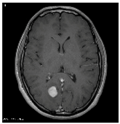

This work collects images from the Kaggle Brain MRI for Brain Tumor Detection dataset, which consists of 253 files with cancer and non-cancer brain images. The sample MRI is illustrated in Figure 2. The dataset has two folders: no tumor encoded as 0 and tumor as 1. The labeled data is more helpful in extracting the patterns from the MRI, which is used to predict the new images related output. The collected image consists of noise information that reduces the performance of brain tumor recognition accuracy. Therefore, image noise should be eliminated to improve the overall prediction efficiency.

Figure 2.

MRI samples Normal Brain MRI (Y1 to Y8) Benign tumor MRI (Y9 to Y15) Malignant tumor MRI (Y16 to Y21).